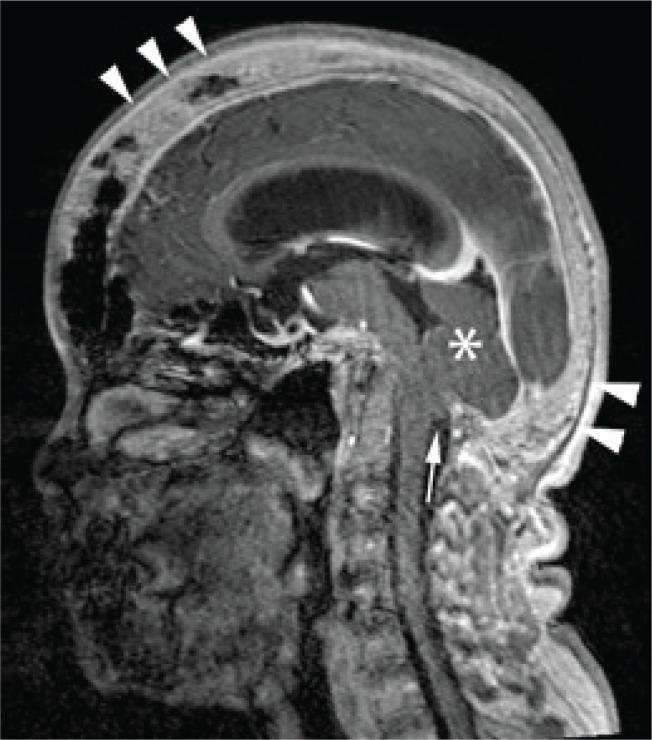

We present the rare case of a 47-year-old woman with protracted primary hyperparathyroidism complicated by communicating hydrocephalus and cerebellar tonsillar herniation secondary to calvarial thickening. The parathyroid glands remained elusive, despite the use of advanced preoperative imaging modalities and three neck explorations. The serum calcium was optimally controlled with cinacalcet and alfacalcidol. Awareness of this rare complication is essential for early diagnosis and prompt intervention to prevent fatal posterior brain herniation.